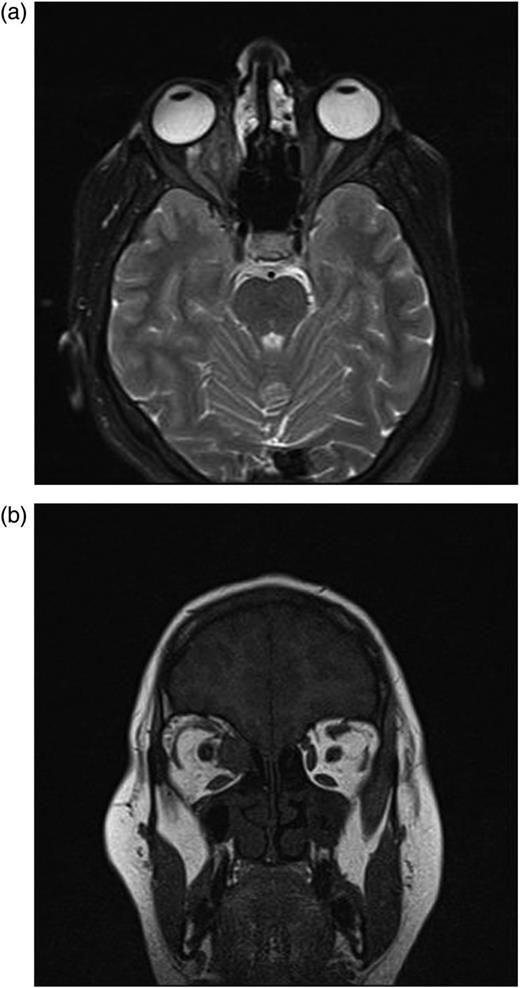

In the second postoperative month, the findings of ocular examination were the same. Control MRI revealed that there was a new small cyst in the intraconal space (Fig. 4a and b). Based on these findings, we planned the second operation via again medial transconjunctival orbitotomy. Peroperatively, we could not find remarkable cyst capsule. To prevent any inoculation, surgery area was washed with %0.9 hypertonic saline solution. Due to the postoperative edema, 80 mg systemic prednisolone was applied for 3 days. Systemic albendazole was applied twice a day for 2 months.

(a and b) After first operation, control MRI in the second postoperative month shows a small cyst displacing optic nerve laterally.